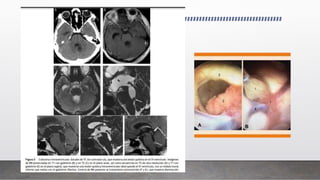

Cisticercos ventriculares

• Representan menos del 33% de todos los casos de neurocisticercosis.

• Los quistes pueden adoptar tamaños variables y generalmente son únicos. El IV ventrículo es el

más afectado (50%), seguido de los ventrículos laterales (35%) y, menos frecuentemente, el III

ventrículo (10%) y el acueducto de Silvio (5%)1,20---22.

• Los parásitos pueden estar adheridos a la capa ependimaria produciendo ventriculitis

(ependimitis granular y gliosis subependimaria) o encontrarse flotando libremente en las

cavidades ventriculares ocasionando obstrucción del líquido cefalorraquídeo.

• Cuando la obstrucción es continua, produce hidrocefalia, y cuando es intermitente, puede dar

lugar al síndrome de Bruns.

antiparasitarios y en estos casos se recomienda terapia de un mes o más con ABZ.

• La NCC Intraventricular: tratamiento quirúrgico y actualmente con la introducción de la

neuroendoscopía; su extirpación con este procedimiento alternativo menos invasivo es alentador.